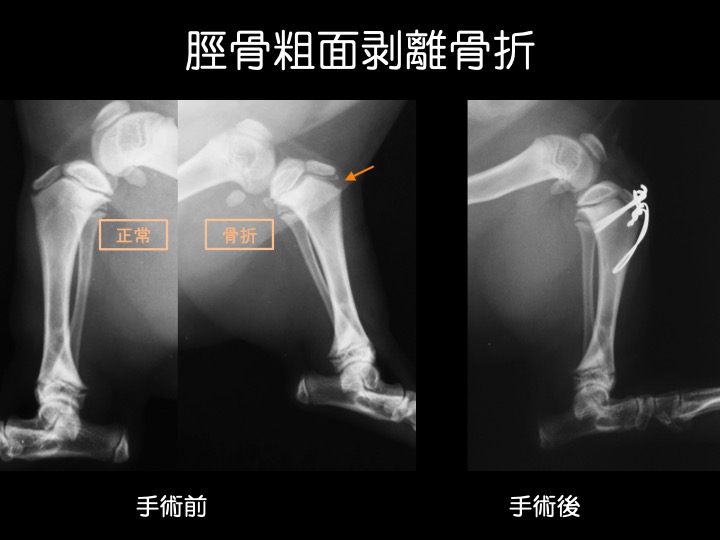

・脛骨粗面(けいこつそめん)はスネの骨の一部の名称で、膝蓋靭帯が付着するために表面がざらざらしており粗面(そめん)と呼ばれています。

・成長期には成長板が開いているため、外傷などが原因で、この部分での剥離骨折が起こります。